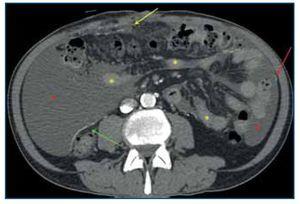

Figura 2.Tomografía computarizada abdominopélvica tras administración de contraste intravenoso, corte axial a nivel de hipogastrio. Se observan calcificaciones lineales «en sábana» del peritoneo parietal (flecha amarilla) y del peritoneo visceral (flecha verde), engrosamiento del mesenterio de las asas intestinales (flecha rosa) por el desarrollo de membranas fibróticas que retraen las asas de intestino delgado adyacentes, así como ascitis loculada (asterisco rojo) en hipogastrio.

Los signos radiológicos de la PE se pueden dividir en tres categorías: anomalías del peritoneo, anomalías en las asas de intestino delgado y la presencia de colecciones líquidas o ascitis loculada3.

La afectación del peritoneo se caracteriza por un engrosamiento de este primero en forma de placas aisladas y más tarde difuso, afectando tanto a la capa de peritoneo visceral como a la parietal3 (figuras 1 y 3). En los estudios de TC realizados tras la administración de contraste intravenoso se puede observar el realce aumentado del peritoneo engrosado2 (figura 3). Las calcificaciones que se producen en el peritoneo comienzan siendo lineales, como pequeñas placas, y evolucionan a calcificaciones «en sábana» (figuras 1-4) y en forma de conglomerados2,3 (figura 4).

Las asas de intestino delgado aparecen engrosadas, con una disminución de su diámetro intraluminal (figuras 1, 3 y 4) y de localización central. También se pueden observar calcificaciones de sus paredes. Como resultado de las membranas fibróticas que se desarrollan envolviéndolas (figuras 2, 3 y 4), la raíz del mesenterio se retrae y se origina un conjunto de adherencias internas, que pueden causar una obstrucción de intestino delgado. En este último caso, las asas se mostrarán dilatadas y como complicación se puede producir necrosis y perforación de estas2,3.

Los pacientes con DP inevitablemente tendrán ascitis3 y, debido al engrosamiento y la fibrosis de las membranas peritoneales, será una ascitis loculada (figuras 1, 2, 3 y 4), que contribuye a la distribución central de las asas de intestino delgado3.